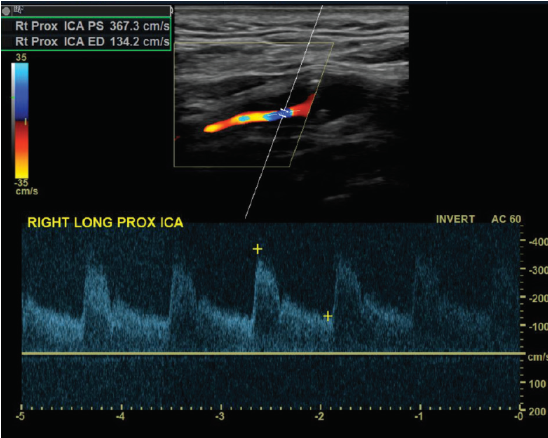

Patient admitted with sudden onset of LT sided weakness and aphasia x 48 hours. Carotid duplex ordered and you obtain this image of RT ICA.

1. Considering patient symptoms, is this a TIA? Why or why not?

2. Considering velocities, what does this image indicate?

3. Describe waveform down stream from this current location.

No because its more than 24 hours

That there is a hemodynamically significant stenosis because the velocities are pretty high at 367.3 cm/s

would be a tardus parvus waveform (slow rise, slow fall)